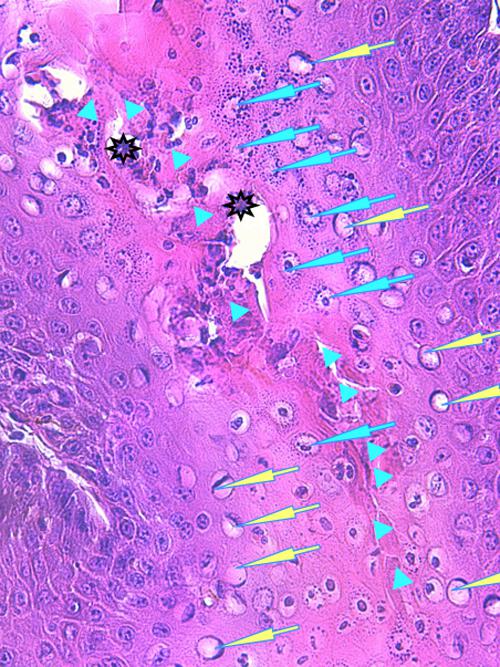

Photo 9 (Hémalun Eosine X 100) peau velue : La couche cornée montre une

stratification de micro-pustules, notamment aux abouchements folliculaires.

Le grand axe d’un infundibulum folliculaire montre une

zone linéaire tortueuse de fissuration et de nécrolyse.

Légendes de la Photo 9 :

- Double flèche pointillée verte : grand axe des infundibula folliculaires

- Double flèche bleue : épiderme

- Double flèche noire : derme

- Ovale jaune : pustules obstruant les abouchements follicualires à l’épiderme

- Flèches jaunes : fissurations linéaires tortueuses cheminant le long des infundibula folliculaires

- Étoiles turquoises pleines : parakératose